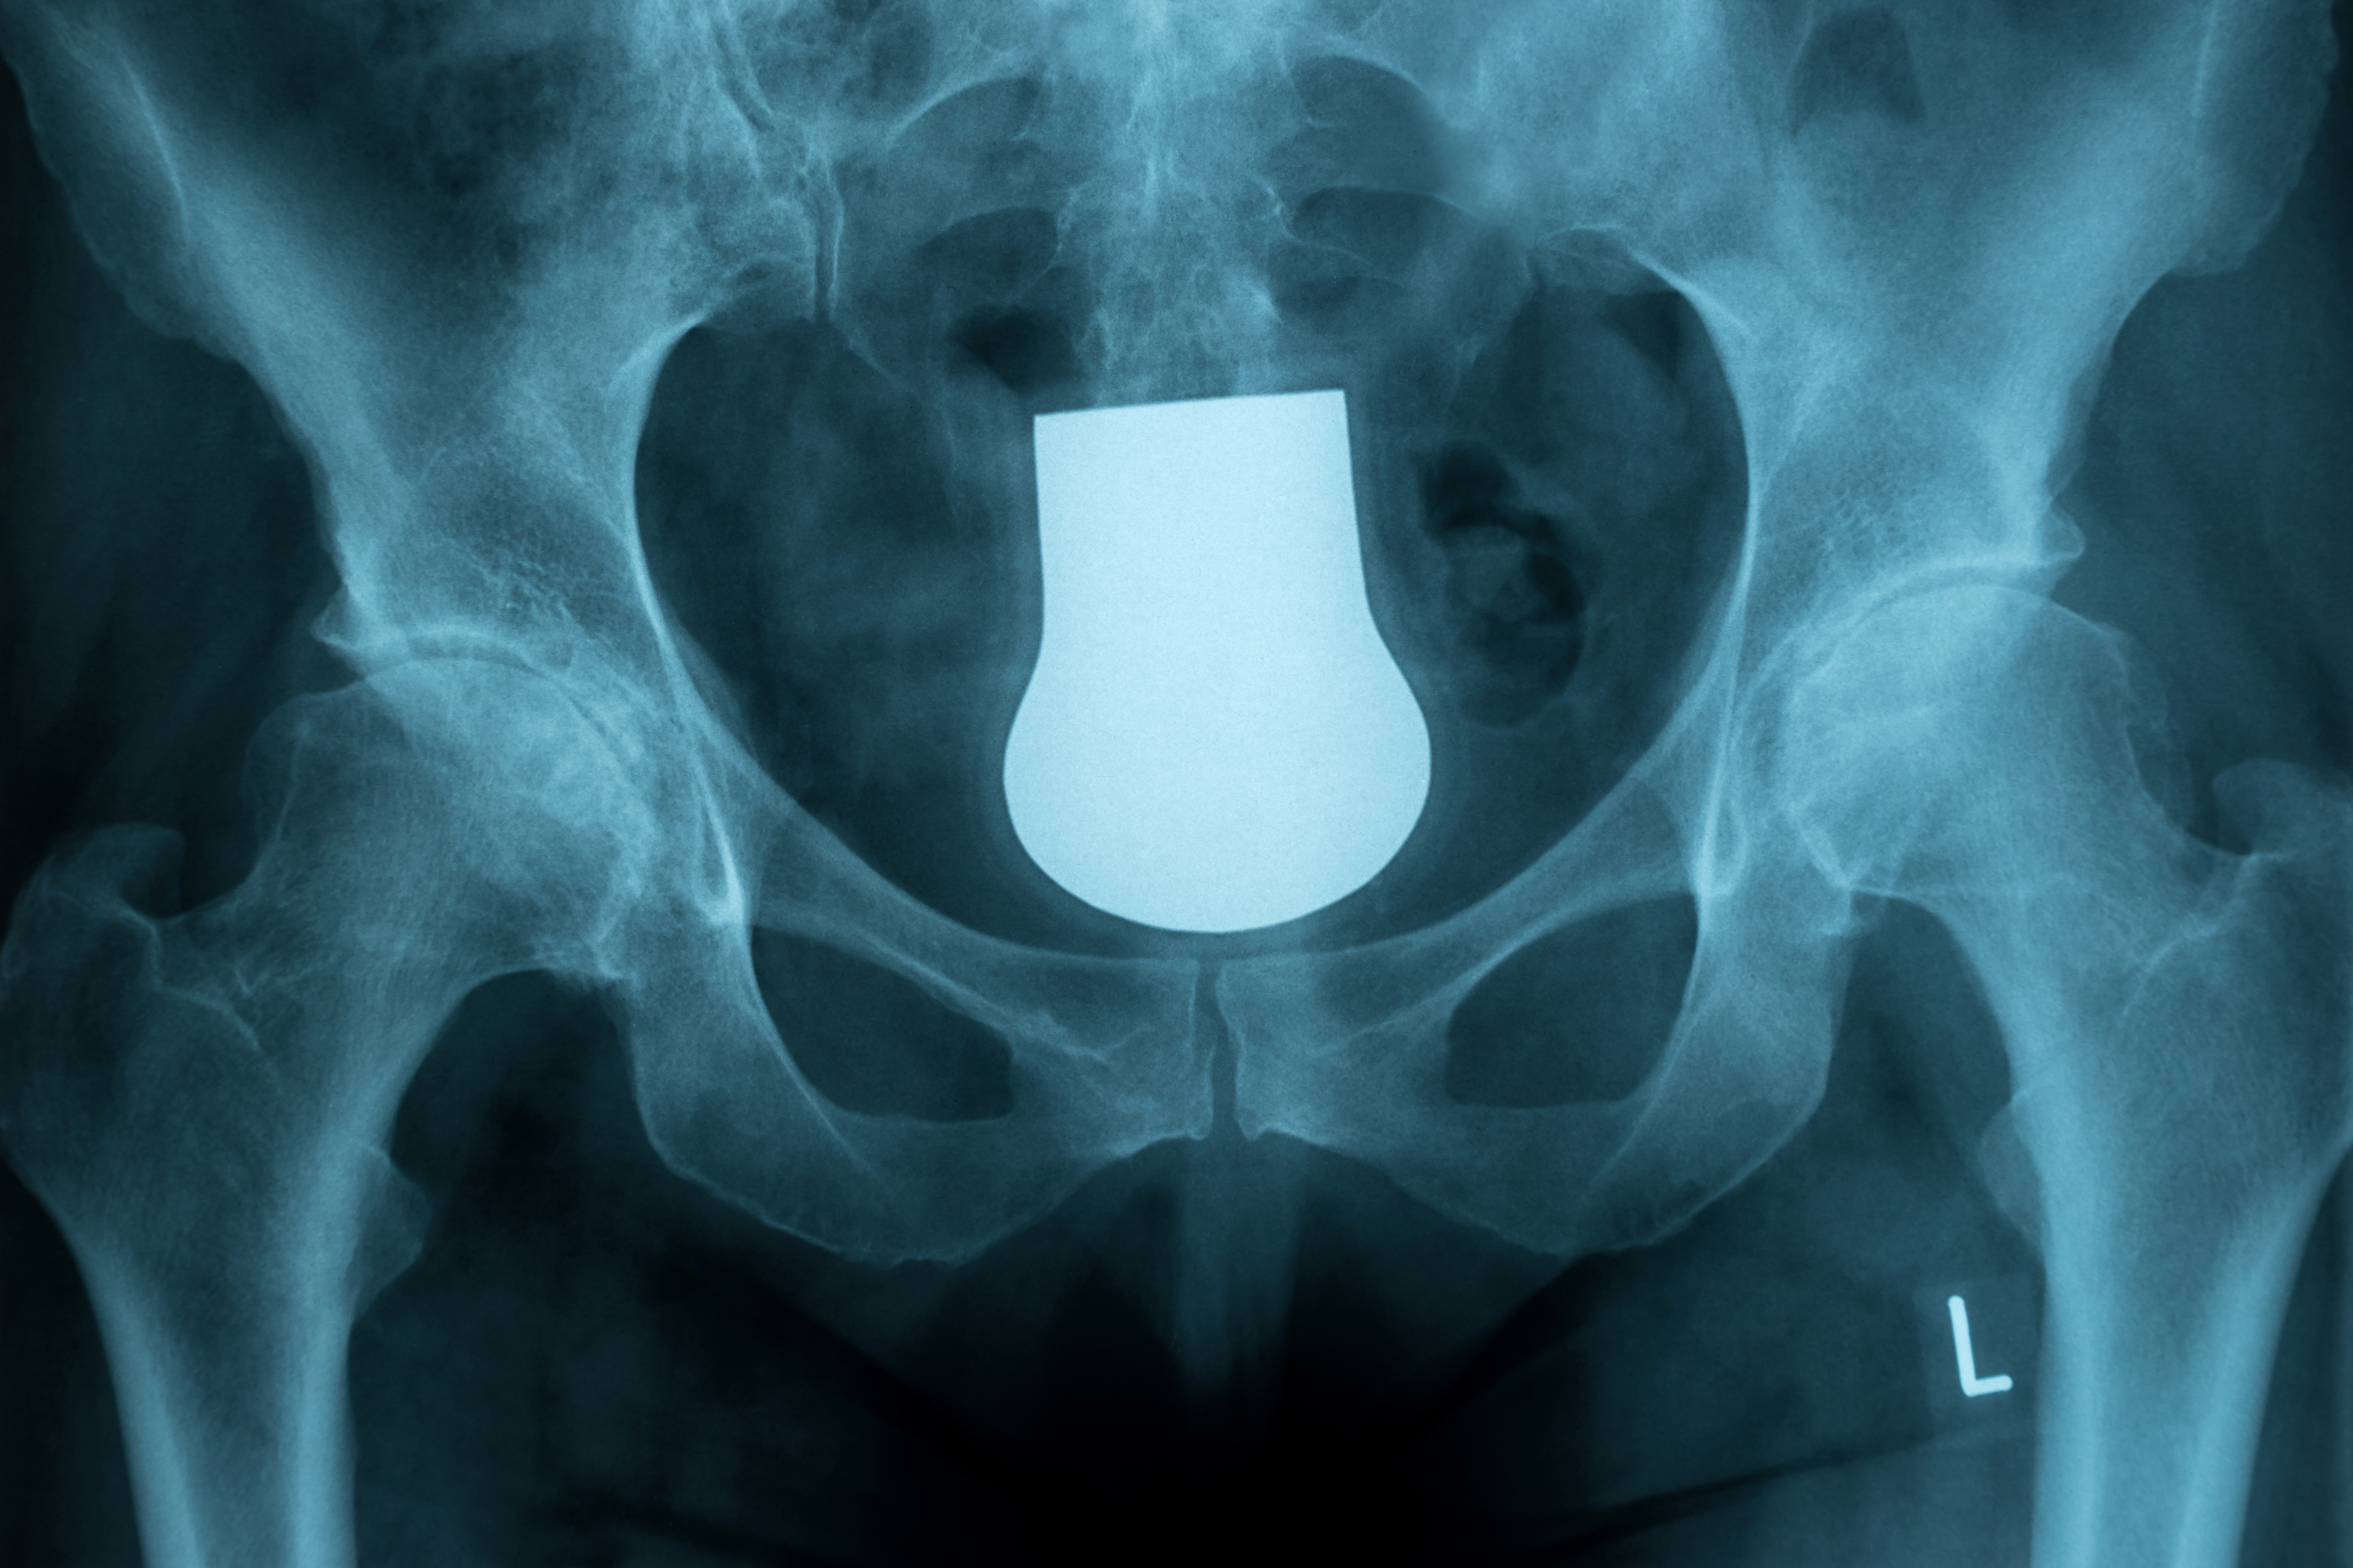

面对髋关节脱位,你的处理方法对吗?

髋关节脱位多为高暴力损伤,暴力间接作用于髋关节导致关节脱位,且髋关节脱位的方向同受伤时的体位有很大相关性。